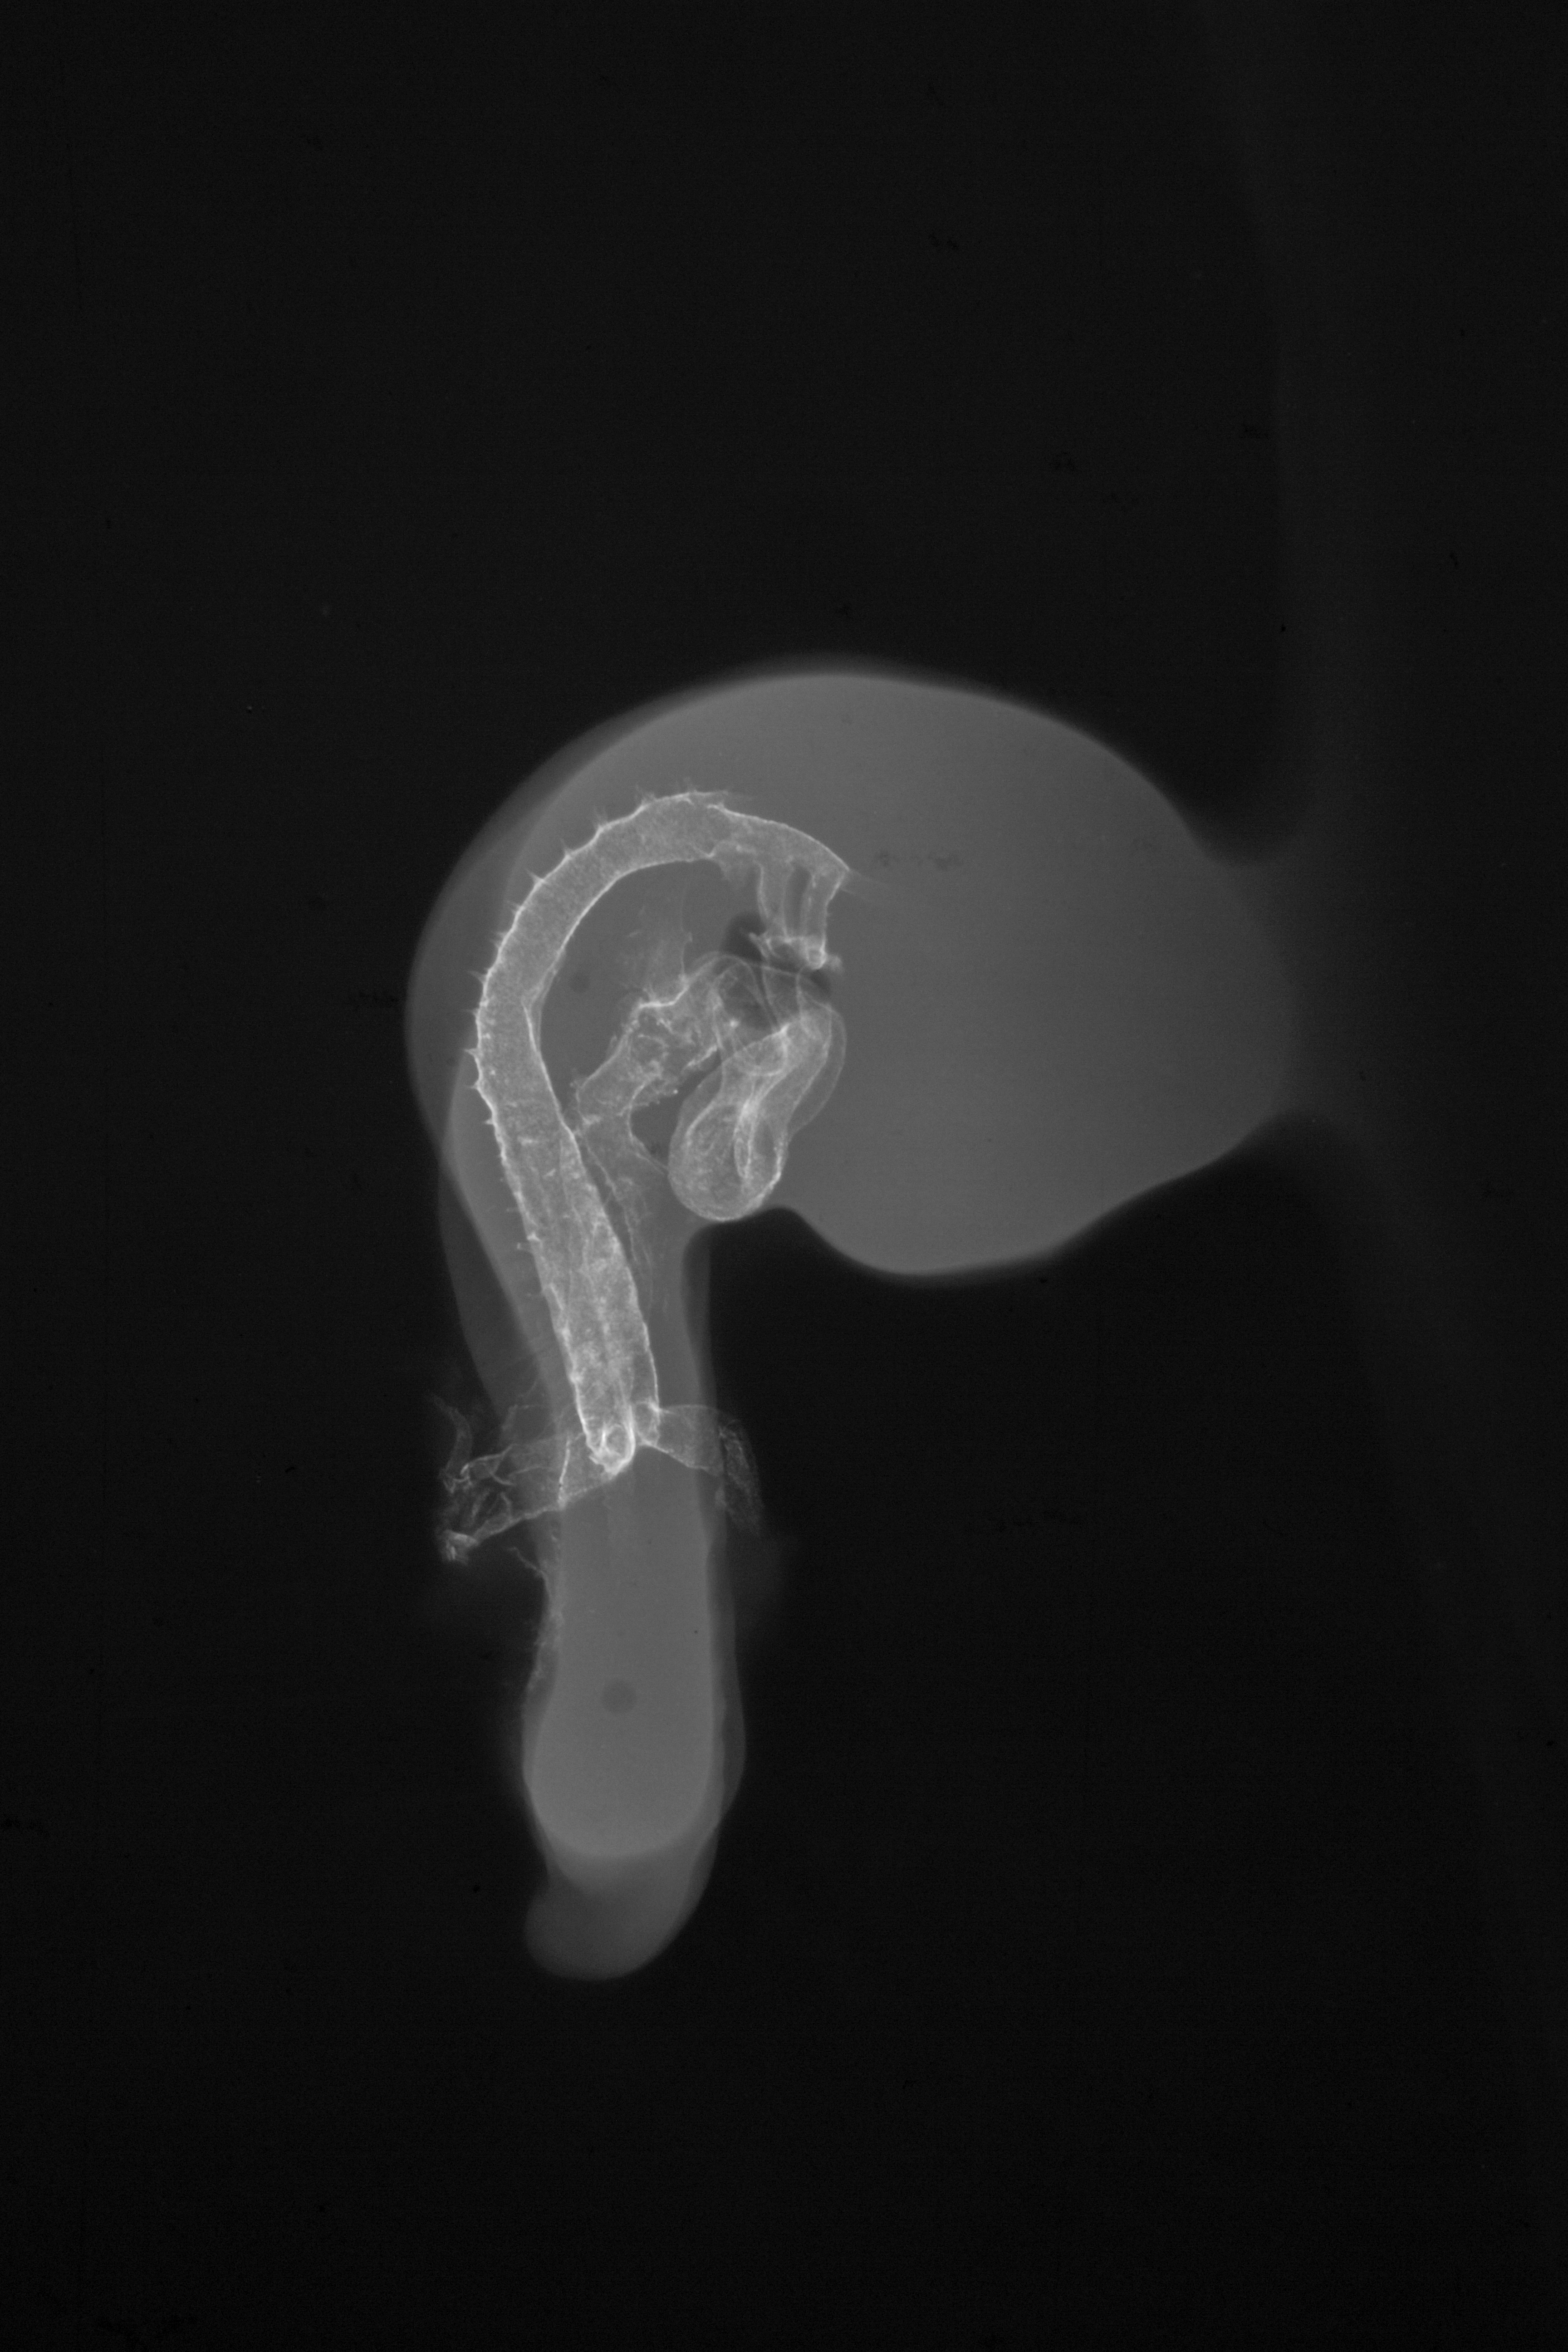

Chick Embryo Microangiography

Hamburger-Hamilton (HH) Stage 18 (approx. 3 days)

X-Ray Micrographs